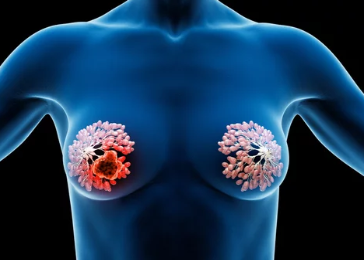

갑상선 유두암은 갑상선 세포에서 발생하는 악성 종양으로, 다음과 같은 특징을 가집니다.

- 가장 흔한 유형: 전체 갑상선암의 약 85%를 차지하는 가장 흔한 형태의 갑상선암입니다.

- 천천히 진행: 암의 진행 속도가 느리며, 조기에 발견하면 치료가 쉽습니다.

- 다른 장기로의 전이 가능성: 드물지만 림프절이나 폐, 뼈 등으로 전이될 가능성도 있습니다.